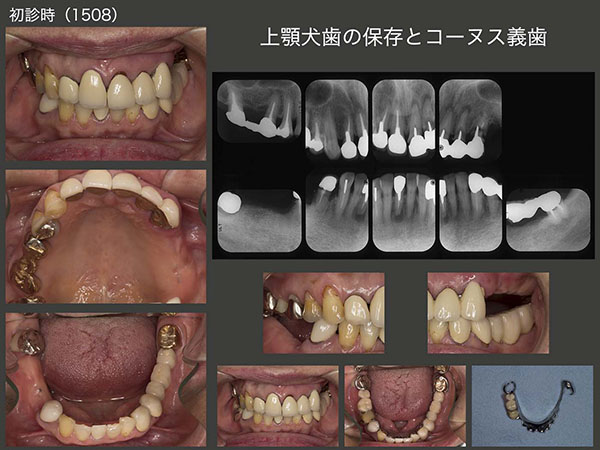

6.上顎犬歯の保存とコーヌス義歯

2015年5月初診,66歳女性.主訴は,上顎左側の前歯が外れそう.デンタルX線写真からみてとれるように左上1〜3は連結冠であり,左上3の歯根破折および左上2,3は歯肉縁下深くまでう蝕が進行していた.連結冠はかろうじて左上1のみで支えられていた.右下にパーシャルデンチャーが装着されているが,維持・安定が悪く,大連結装置が必要以上に大きかった.患者さんは,上下に咬合支持歯がある右側で主に咀嚼していたが,右下8が負担に耐えられず痛くなったので,つい左側でも咀嚼してしまい,直ぐに左上3の歯根破折が生じた.つぎに梃子作用により左上2のセメントアウト,カリエスに繋がったと推測できる.なお上顎には,義歯が装着されていなかった.